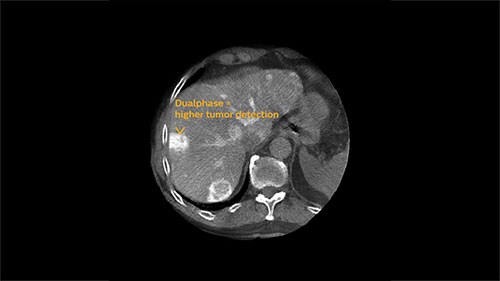

XperCT Dual allows two phases of a contrast injection to be displayed next to each other. Clinicians can assess the feeder vessels to a tumor in the arterial phase and see the tumor boundaries in the delayed phase. Studies have shown that this novel method is superior to conventional DSA and provides equivalent imaging information to the gold standard of contrast enhanced MRI.³ ⁶

EmboGuide is based on XperCT Dual, a dedicated type of 3D oncologic imaging, which is used to visualize tumors and their feeding vessels.

Arterial phase

Delayed phase